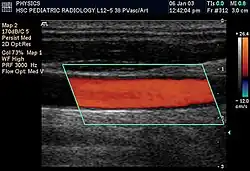

Duplex scan of the common carotid artery

Doppler ultrasonography employs the Doppler effect to assess whether structures (usually blood)[58][61] are moving towards or away from the probe, and their relative velocity. By calculating the frequency shift of a particular sample volume, flow in an artery or a jet of blood flow over a heart valve, its speed and direction can be determined and visualized, as an example. Color Doppler is the measurement of velocity by color scale. Color Doppler images are generally combined with gray scale (B-mode) images to display duplex ultrasonography images.[62] Uses include: